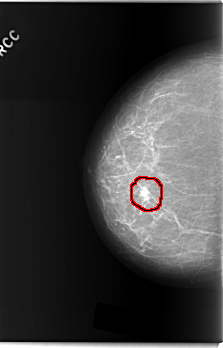

C_0209_1.RIGHT_MLO

FILE: C_0209_1.RIGHT_MLO.OVERLAY

TOTAL_ABNORMALITIES 1

ABNORMALITY 1

LESION_TYPE MASS SHAPE OVAL MARGINS MICROLOBULATED

ASSESSMENT 5

SUBTLETY 5

PATHOLOGY MALIGNANT

TOTAL_OUTLINES 1

BOUNDARY

FILE: C_0209_1.RIGHT_CC.OVERLAY

LESION_TYPE MASS SHAPE LOBULATED MARGINS MICROLOBULATED